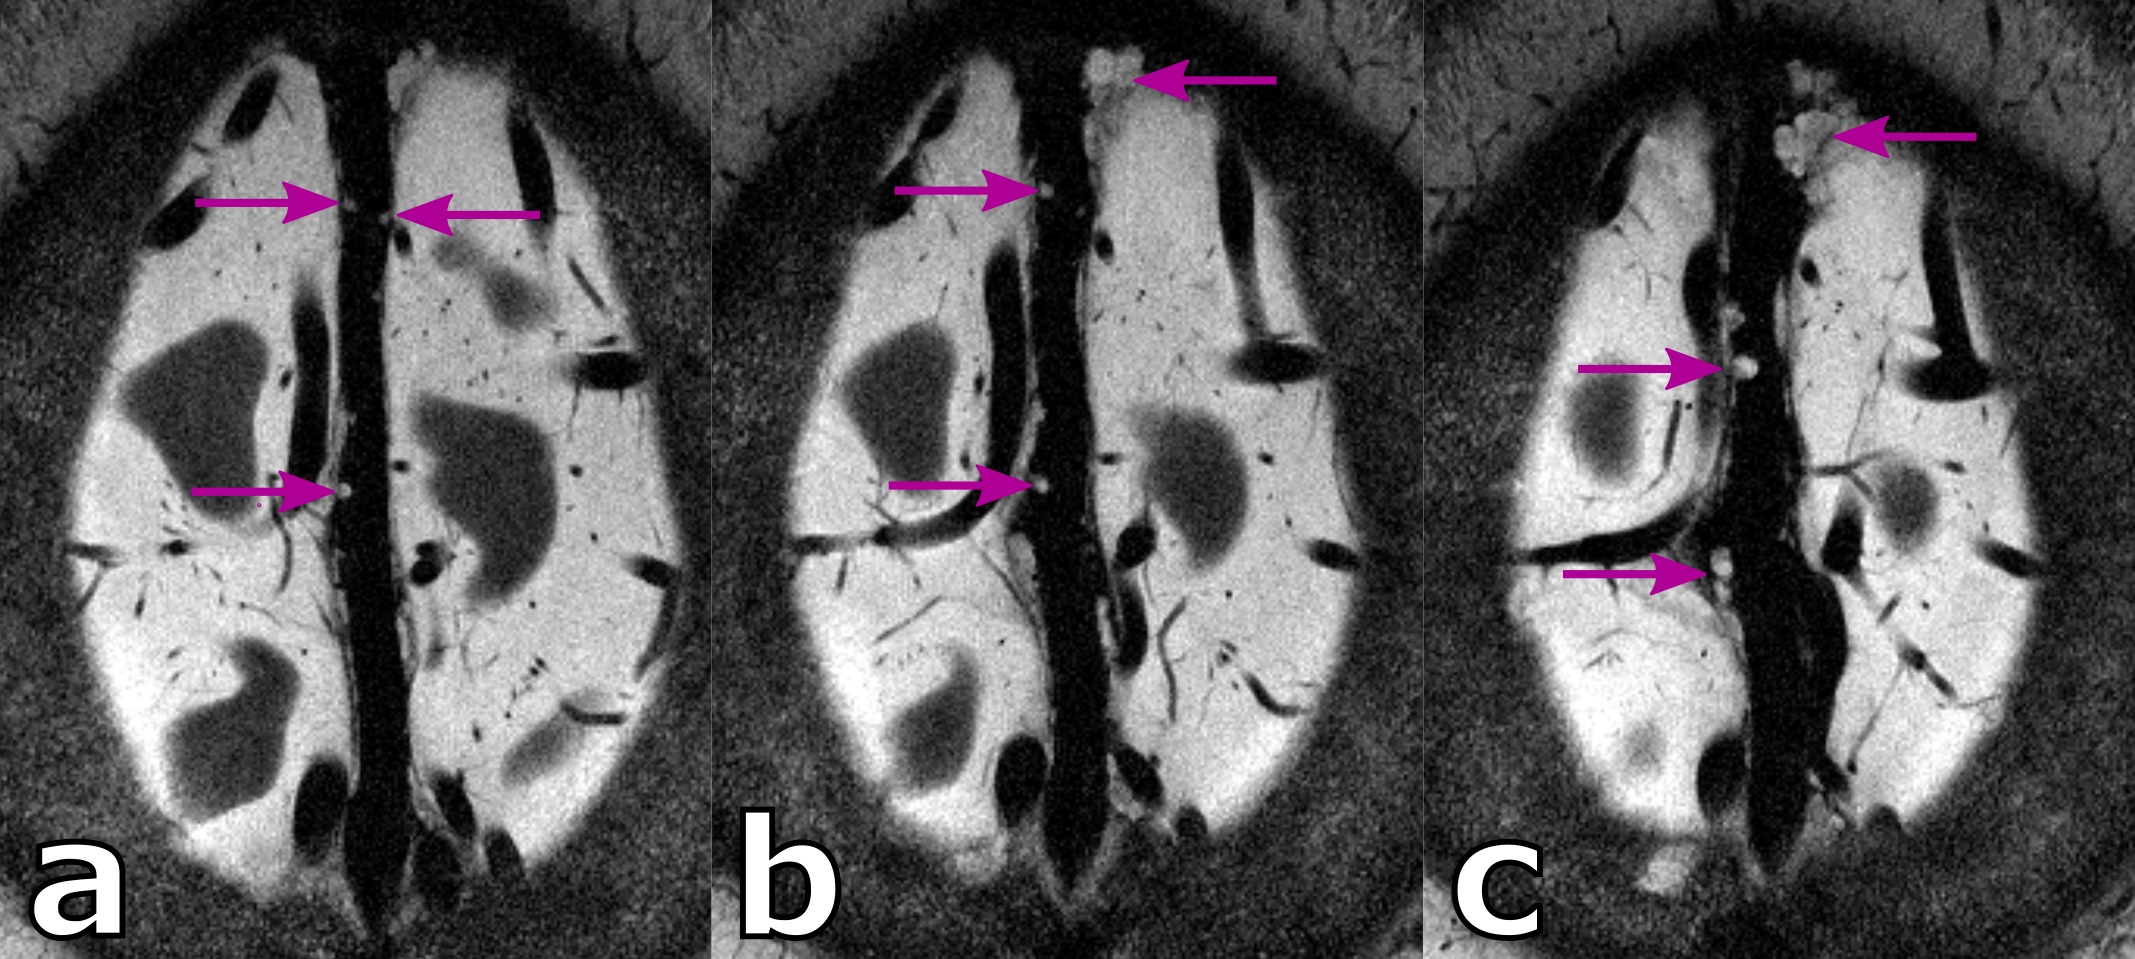

Figure 2: Ultra high resolution, axial slices of a healthy 38 years old male showing perivascular spaces (green boxes). Zoomed in versions in (b) and (c) show clearly vessels within some perivascular space (green arrows). Hyperintense structures in the sinus (magenta box) and slices positioned 1 cm above and below (d),(f) show hyperintense structures penetrating through the venous vessels.

For the 38 years old volunteer (see Fig.2-4) similar hyperintense structures in the sinus and a noteworthy amount of PVS can be seen. With the ultra-high resolution used in this study, in five PVS the corresponding vessel inside the PVS itself can be depicted at least partially. This is an observation uncommon at lower resolutions and, to our best knowledge not described in the literature to date. For the five spaces with a vessel inside, the average ± standard deviation was 1.62 ± 0.14 and 0.11 ± 0.05 for the vessel-to-PVS signal ratio and vessel-to-PVS volume ratio, respectively. Hence, only a minor volume fraction of the PVS with vessels is actually occupied by the vessel. While the signal ratio for the detected vessel segment is sufficient for detection, the remaining vessel segments are no depicted, most likely due to partial volume effects. This might be in part driven by the anisotropic resolution. In the thick slices, the majority of detected vessel segments was oriented perpendicular to the slices. Hence, for sufficient vessel-to-PVS ratio independent of the vessel and slice orientation isotropic resolutions are favorable.